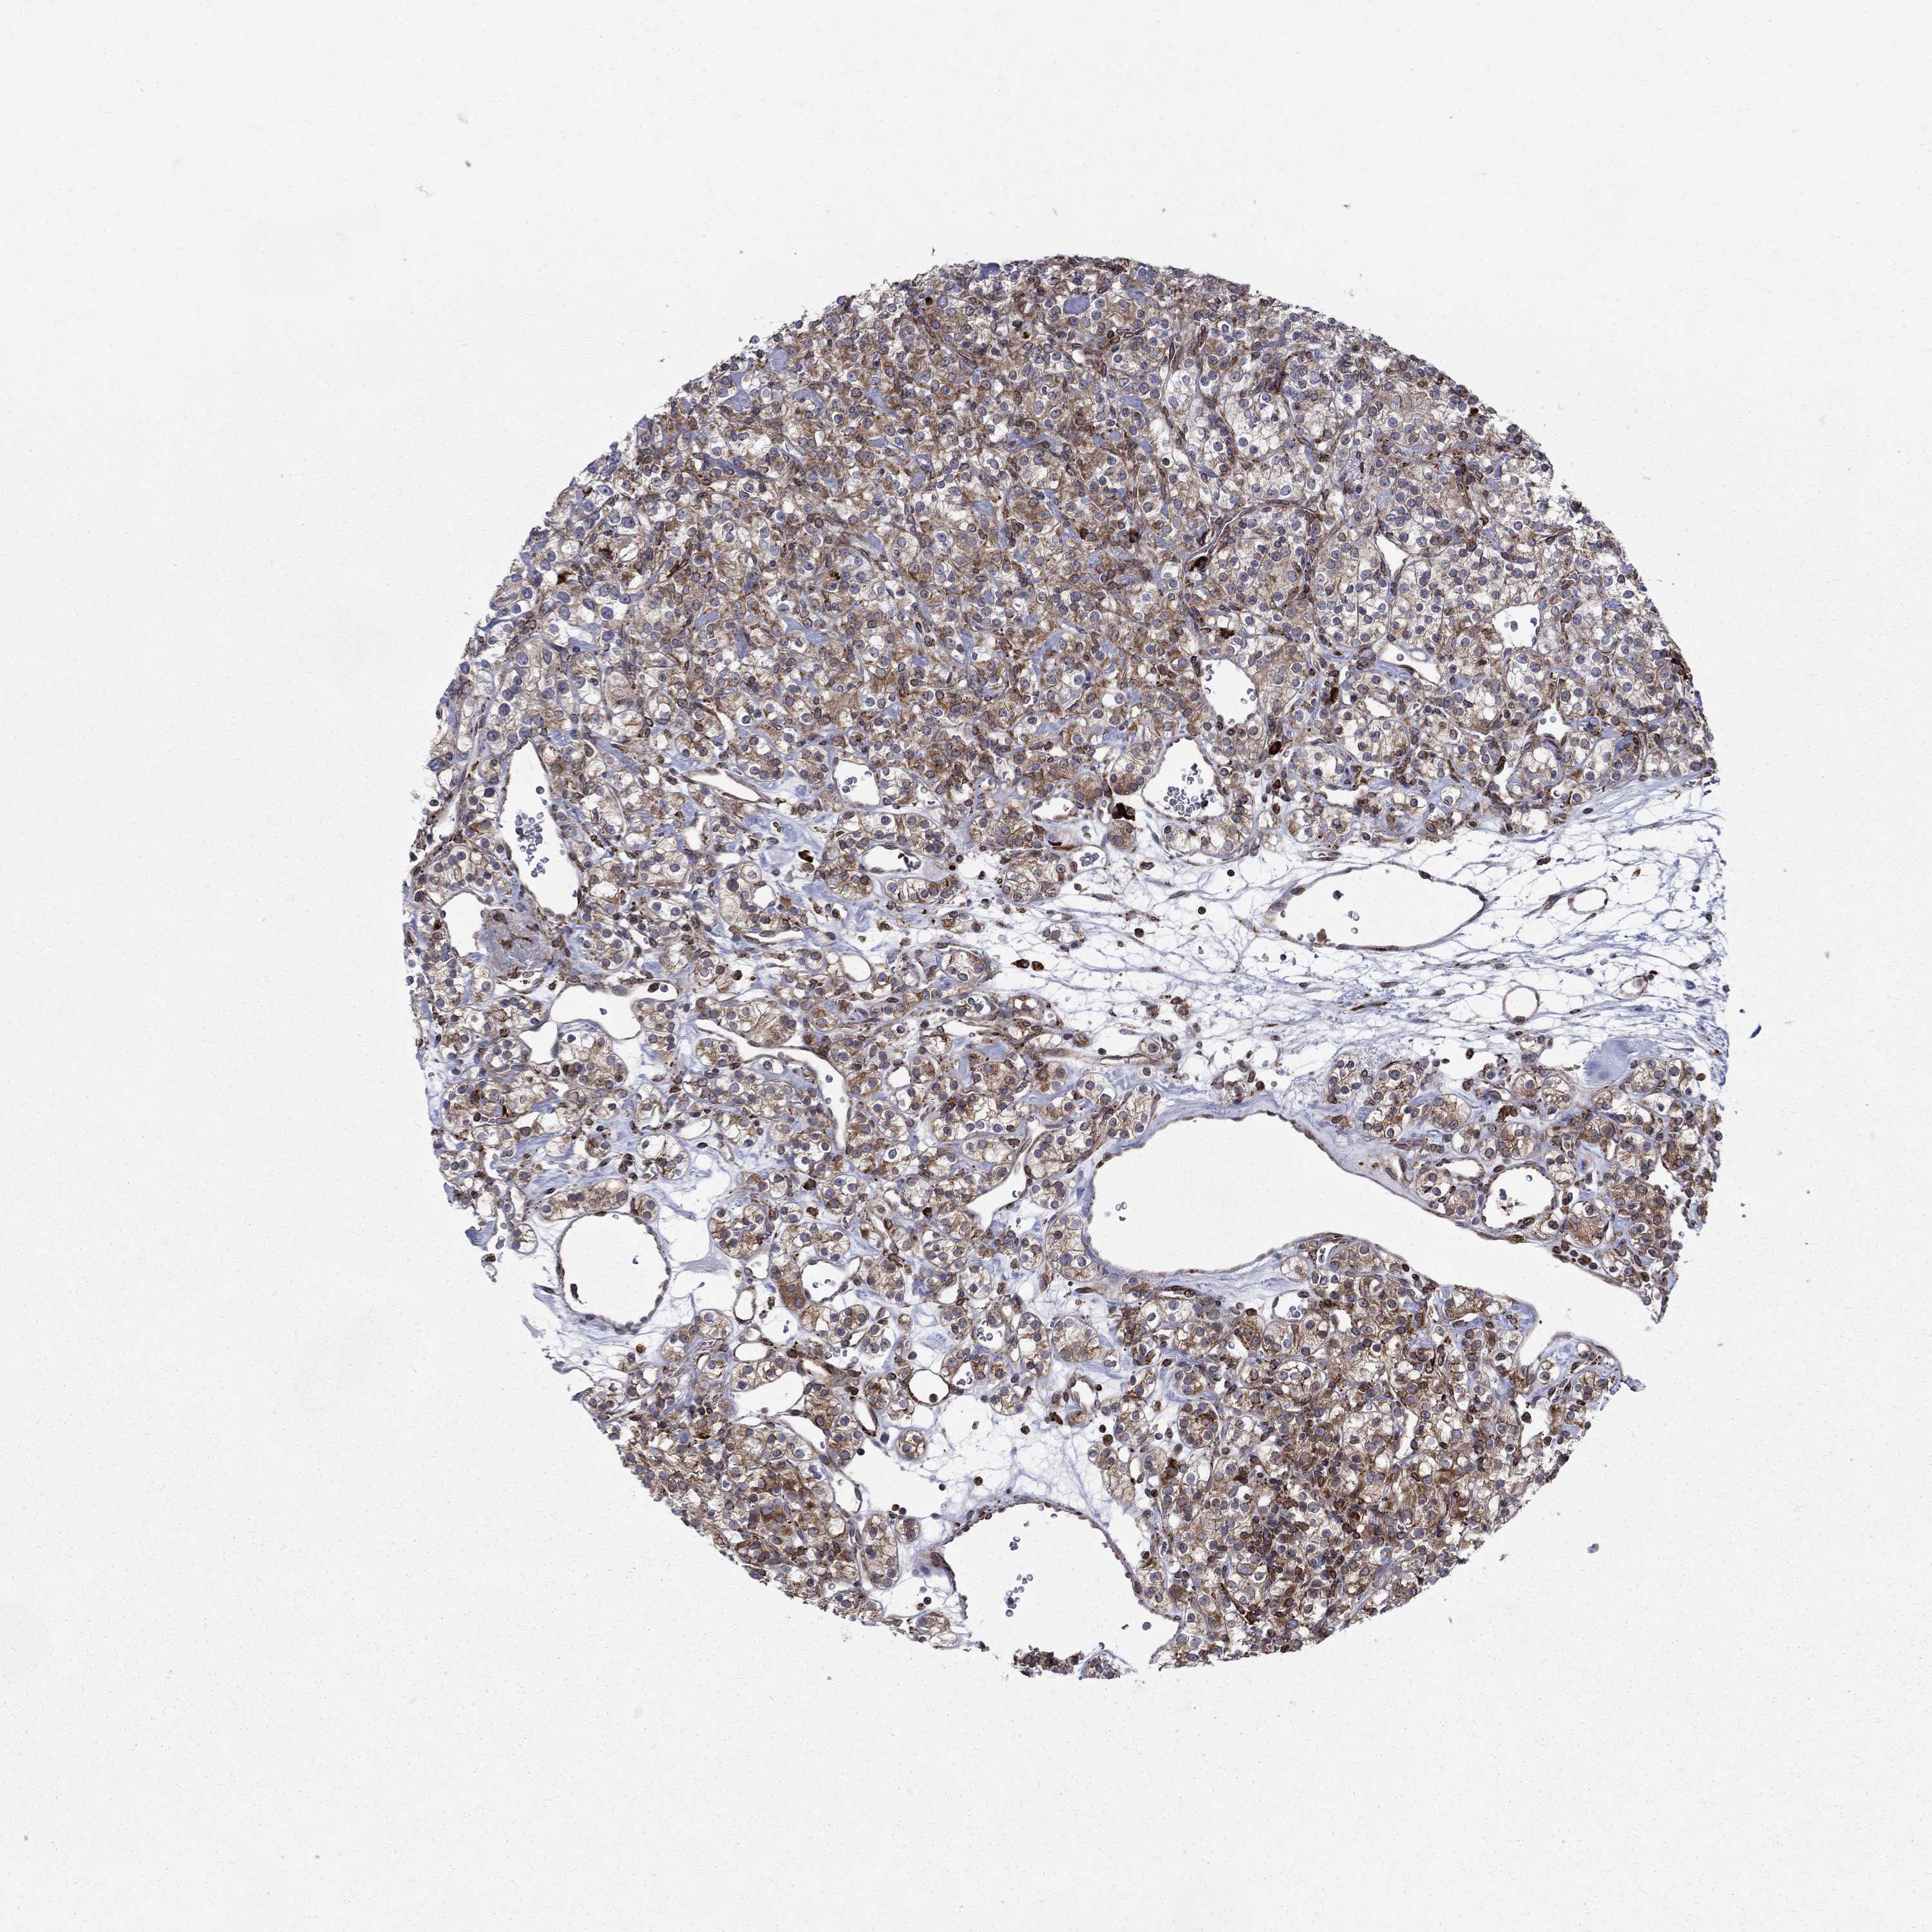

KIDNEY RENAL CLEAR CELL CARCINOMA (TCGA) - Interactive survival scatter ploti

The Survival Scatter plot shows the clinical status (i.e. dead or alive) for all individuals in the patient cohort, based on the same data that underlies the corresponding Kaplan-Meier plots. Patients that are alive at last time for follow-up are shown in blue and patients who have died during the study are shown in red.

The x-axis shows the expression levels (FPKM) of the investigated gene in the tumor tissue at the time of diagnosis. The y-axis shows the follow-up time after diagnosis (years). Both axes are complimented with kernel density curves demonstrating the data density over the axes. The top density plot shows the expression levels (FPKM) distribution among dead (red) and alive patients (blue). The right density plot shows the data density of the survived years of dead patients with high and low expression levels respectively, stratified using the cutoff indicated by the vertical dashed line through the Survival Scatter plot. This cutoff is automatically defined based on the FPKM cutoff that minimizes the p-score. The cutoff can be changed by dragging the vertical line or by entering a cutoff value in the square labeled "Current cut-off".

Under the Survival Scatter plot the p-score landscape (black curve; left axis) is shown together with dead median separation (red curve; right axis). Dead median separation is the difference in median mRNA expression between patients who have died with high and low expression, respectively. It is calculated as follows: median FPKM expression of dead patients with high expression - median FPKM expression of dead patients with low expression. This is intended to aid the user in visually exploring custom cutoffs and the associated p-scores and dead median separation.

Individual patient data is displayed and can be filtered by clicking on one or more of the category buttons on the top of the page. Categories describing expression level and patient information include: high, low, alive, dead, female, male and tumor stages. The scale of the x-axis can be toggled between linear and log-scale by clicking on the "x log" button. Mouse-over function shows TCGA ID, patient information and mRNA expression (FPKM) for each patient.

& Survival analysisi

Kaplan-Meier plots summarize results from analysis of correlation between mRNA expression level and patient survival. Patients were divided based on level of expression into one of the two groups "low" (under cut off) or "high" (over cut off). X-axis shows time for survival (years) and y-axis shows the probability of survival, where 1.0 corresponds to 100 percent.

CAB39L is potential prognostic, high expression is favorable in Kidney Renal Clear Cell Carcinoma (TCGA)

Best expression cut offi

Based on the FPKM value of each gene, patients were classified into two groups and association between prognosis (survival) and gene expression (FPKM) was examined. The best expression cut-off refers the FPKM value that yields maximal difference with regard to survival between the two groups at the lowest log-rank P-value. Best expression cut-off was selected based on survival analysis .

When clicking on this number, the vertical dashed line indicating cut-off, the interactive survival plot, and the Kaplan-Meier curve will be adjusted to show results based on the best expression cut-off.

: 3.83

TCGA RNA samplesi

RNA-seq data is reported as average FPKM (number Fragments Per Kilobase of exon per Million reads), generated by the The Cancer Genome Atlas (TCGA) .

Normal distribution across the dataset is visualized with box plots, shown as median and 25th and 75th percentiles. Points are displayed as outliers if they are above or below 1.5 times the interquartile range. FPKM values of the individual samples are presented next to the box plot.

Average pTPM 6.4

Number of samples 521